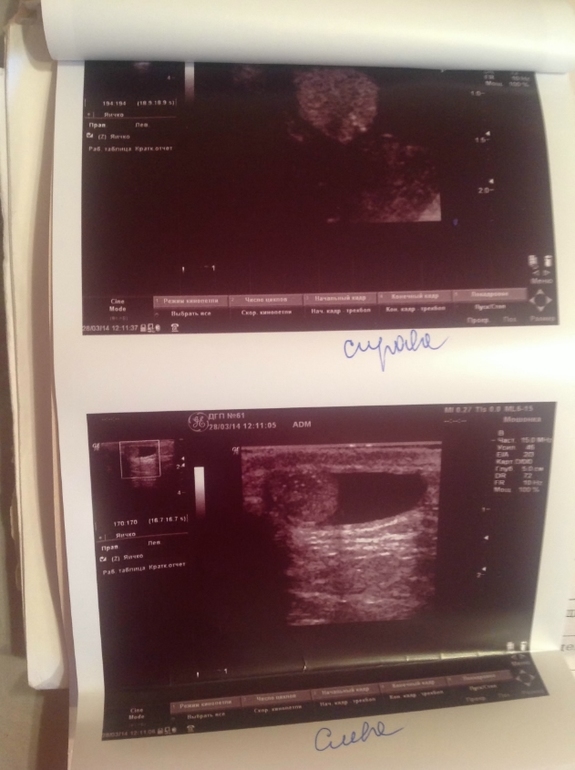

Здравствуйте Максим Викторович! Подскажите, пожалуйста! У сына с рождения водянка, хирург говорил, что можно подождать до 3 лет. Сейчас ему 2г9мес. Сегодня сделали узи. Помимо водянки на левом яичке гипоэхогенные включения и гипоэхогенная структура. Что это и чем это грозит? Нас направили к урологу, но попадём к нему только на следующей неделе. Сейчас всякие разные мысли плохие лезут в голову. И стоит ли оперировать данную водянку? Хирург говорил, что если там жидкости очень мало, то не стоит ничего делать. А мало это сколько?

Это так называемый синдром "звездного неба" или синдром "гиперэхогенных включений" в яичке. Что бы сказать что то конкретное, мне надо бы вас смотреть самому и на УЗИ аппарате экспертного класса. Это может и ни о чем не говорить, а может свидетельствовать о наличии проблемы, нужна качественная оценка ситуации и не только по УЗИ